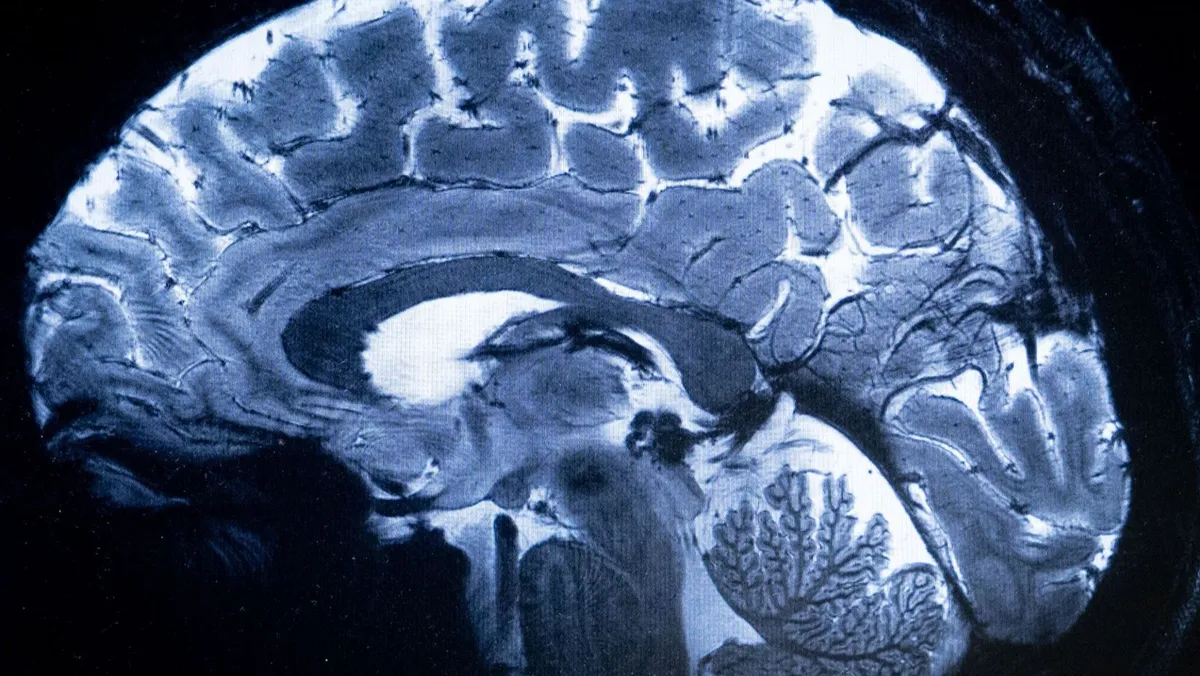

أثبتت تجربة بحثية أن الخلايا الدماغية البشرية قادرة على البقاء على قيد الحياة، خلال تواجدها في مدار الأرض المنخفض لأسابيع طويلة، وفق نتائج دراسة منشورة حديثاً، ما يفتح الباب أمام تطوير علاجات لأمراض مستعصية.

قاد فريق من الباحثين، بقيادة عالم الأحياء الجزيئية دافيدي ماروتا من مختبر المحطة الفضائية الدولية الوطني، دراسة لاستكشاف تأثيرات الجاذبية الدقيقة على الدماغ البشري، مع التركيز على الخلايا العصبية المتأثرة بالأمراض العصبية الانتكاسية مثل التصلب المتعدد، ومرض باركنسون.